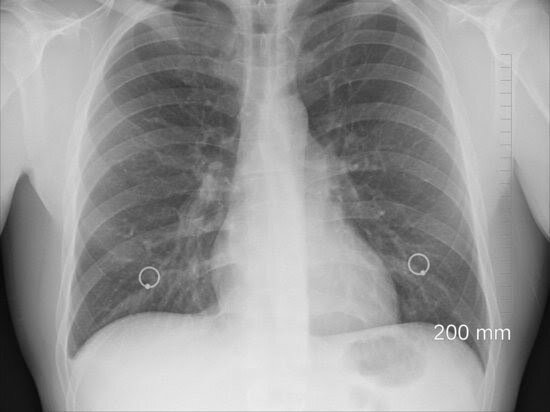

😰 Вчера в Севастополе выписали первого пациента, госпитализированного с диагнозом COVID-19, но его легкие сохранились только на 30% «Вот сегодня выписан пятый заболевший коронавирусом, он был из первой пятерки госпитализированных и сегодня он покинул больницу, 70% легких — белое пятно, то есть 30% сохранилось. Да, будет регенерация, но насколько она произойдет — непонятно», — рассказал врио губернатора города Михаил Развожаев. Он добавил, что фактически такое состояние означает инвалидизацию.

«Вот сегодня выписан пятый заболевший коронавирусом, он был из первой пятерки госпитализированных и сегодня он покинул больницу, 70% легких — белое пятно, то есть 30% сохранилось. Да, будет регенерация, но насколько она произойдет — непонятно», — рассказал врио губернатора города Михаил Развожаев. Он добавил, что фактически такое состояние означает инвалидизацию.